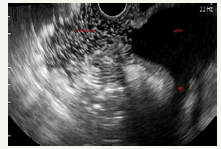

SCN is a cystic neoplasm filled with serous fluid, originating from centroacinar cells and consisting of cubic glycogen-rich cells [10]. SCN is more common in women, most often in the sixth - seventh decade of life (50-60 years) [12]. The median age is 68 years [45]. Due to its benign nature, such tumors can grow to large sizes, without any symptoms [46]. Usually SCN is a single cyst, of a rounded shape, consisting of many small cysts, ranging in size from millimeters to several centimeters. The presence of microcystic component is called the sign of “honeycomb”, which is characteristically of this type of neoplasm [47] (Figure 9A-9C). Often in the center of the tumor can be located fibrous scar [12,25,33]. The inner surface of the cyst is lined with a single layer of cubic epithelium. The outer wall and the inner septs of the tumor of a good blood supply. SCN does not communicate with the pancreatic duct. The cyst is filled with a clear serous fluid.

Figure 9A:Clinical case of SCN in 42 years old woman.

Figure 9B:EUS view of the neoplasm (in the red oval). On EUS imaging we can very well see “honeycomb” sing.

Figure 9: Clinical case of SCN in 42 years old woman.